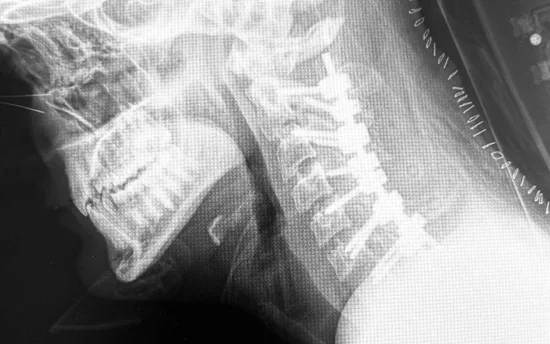

Cifosis post-laminectomía cervical

La cifosis post-laminectomía cervical es una curvatura anormal hacia adelante de la columna cervical (cuello) que puede ocurrir después de una laminectomía, que es un tipo de cirugía de columna. Esta condición puede resultar de la eliminación de parte de la lámina, que es una estructura ósea que cubre y protege la médula espinal, lo que puede alterar la estabilidad y la alineación de la columna vertebral. La gravedad de la cifosis y los síntomas asociados pueden variar y, en consecuencia, las estrategias de tratamiento también

Fusión Espinal: Unir dos o más vértebras utilizando injertos óseos y/o dispositivos de fijación como tornillos y barras para estabilizar y corregir la alineación de la columna vertebral.